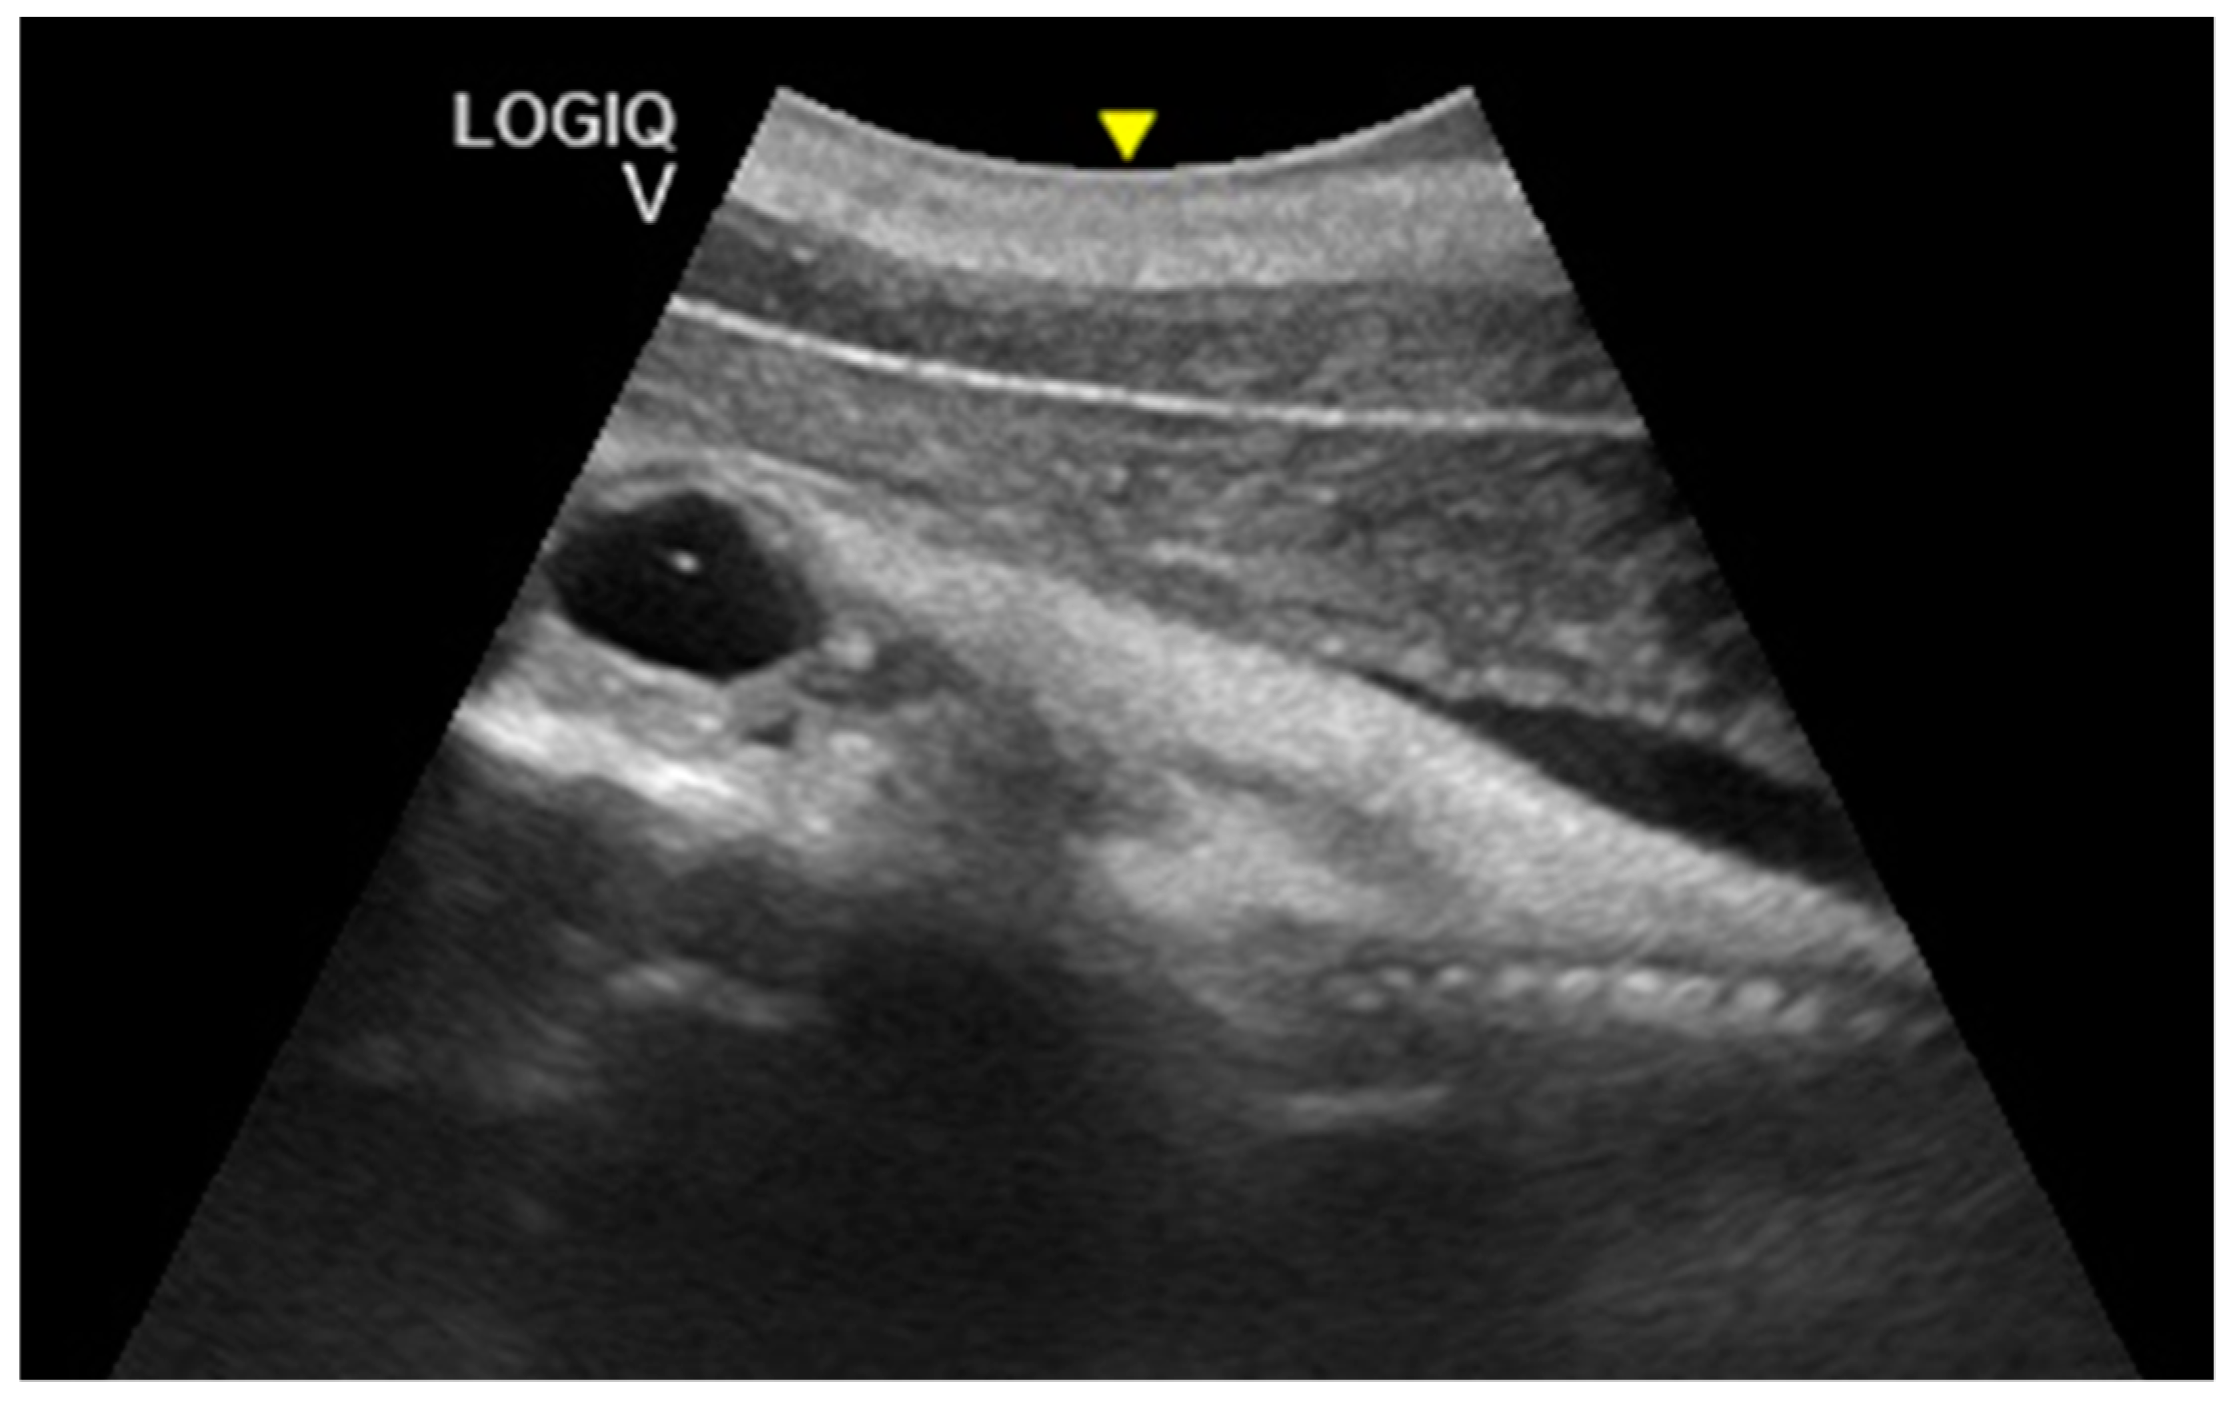

The intestine was visualized at 189 ± 5 days of gestation. The cardiac chambers were visualized 194 ± 5 days after ovulation, and after about 3 weeks, the vascular structures (aorta and caudal vena cava) departing from them were visualized (Figure 7).

Figure 7.

Fetal spinal cord (Sp), stomach (S), liver (Li), intestine (I), lungs (Lu), and heart (H) were visualized at 194 ± 5 days of gestation.